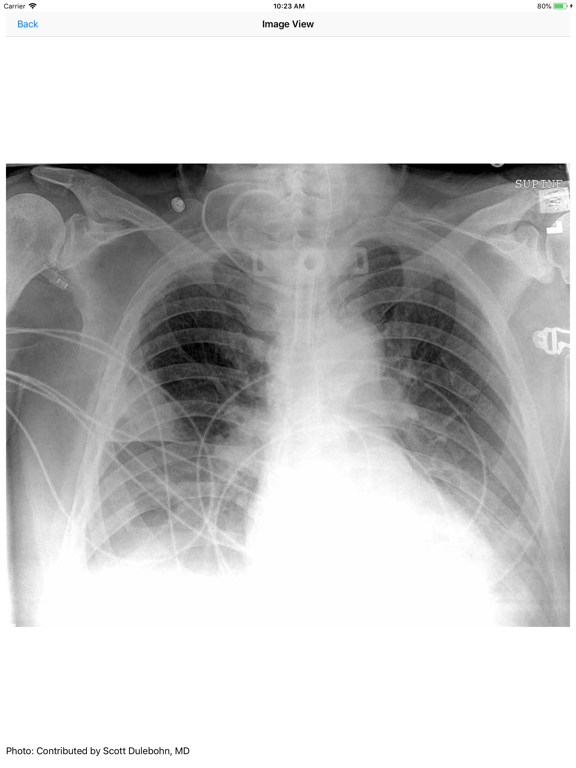

Screenshots